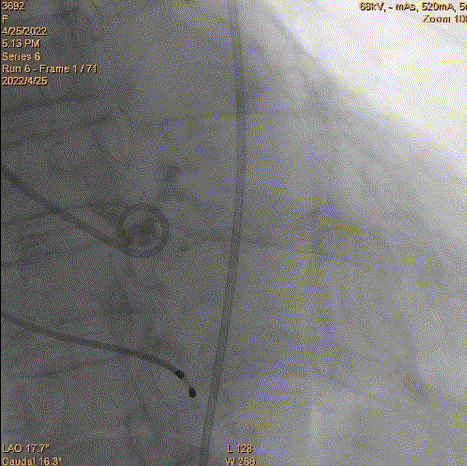

3、球囊预扩:由于钙化严重球囊无法通过,遂使用圈套器抓捕球囊。

套圈器抓球囊过瓣

20mm球囊预扩

导丝位置改变

对侧上圈套器准备

4、跨瓣:瓣膜跨瓣出现困难,计划使用圈套器。由于没有22F大鞘,内连鞘无法拆卸,选择左侧穿刺导入导管。右侧双导丝,送入Lunderquist,心室较大。扩张后,血压较稳定。经尝试无法退球囊,撤出系统。通过对侧使用抓捕器,将导丝全撤,导入AL1.0导管重新跨瓣。鉴于左侧入路有角度,使用泥鳅导丝带上导管,做圈套器。顺利抓住J型导丝,抓捕器顺利抓捕瓣膜过瓣。